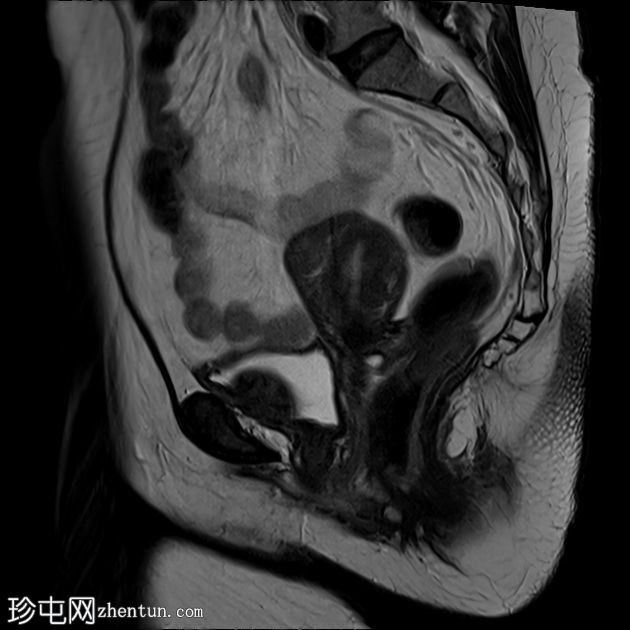

矢状位

T2加权像

可见膀胱左侧壁有一边界清晰的T2低信号实

性病

灶,无扩散受限,均匀强化。未见膀胱周围侵犯或肾积水。

子宫底部前壁可见一小肌瘤。双侧卵巢可见无强化囊肿。盆腔及腹股沟未见异常淋巴结肿大。

这是一例经组织学证实的膀胱平滑肌瘤病例。